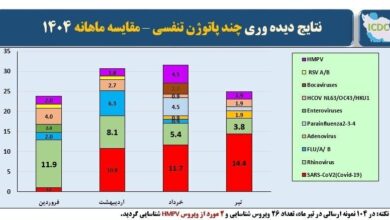

هشدار مهم! این بیماری را به بالای بیماریهای تنفسی کشور برگردانید

آخرین نتایج نظارت بر ویروس های موجود در بیماریهای حاد تنفسی در کشور ، بازگشت ویروس تاج به بالای ویروس…